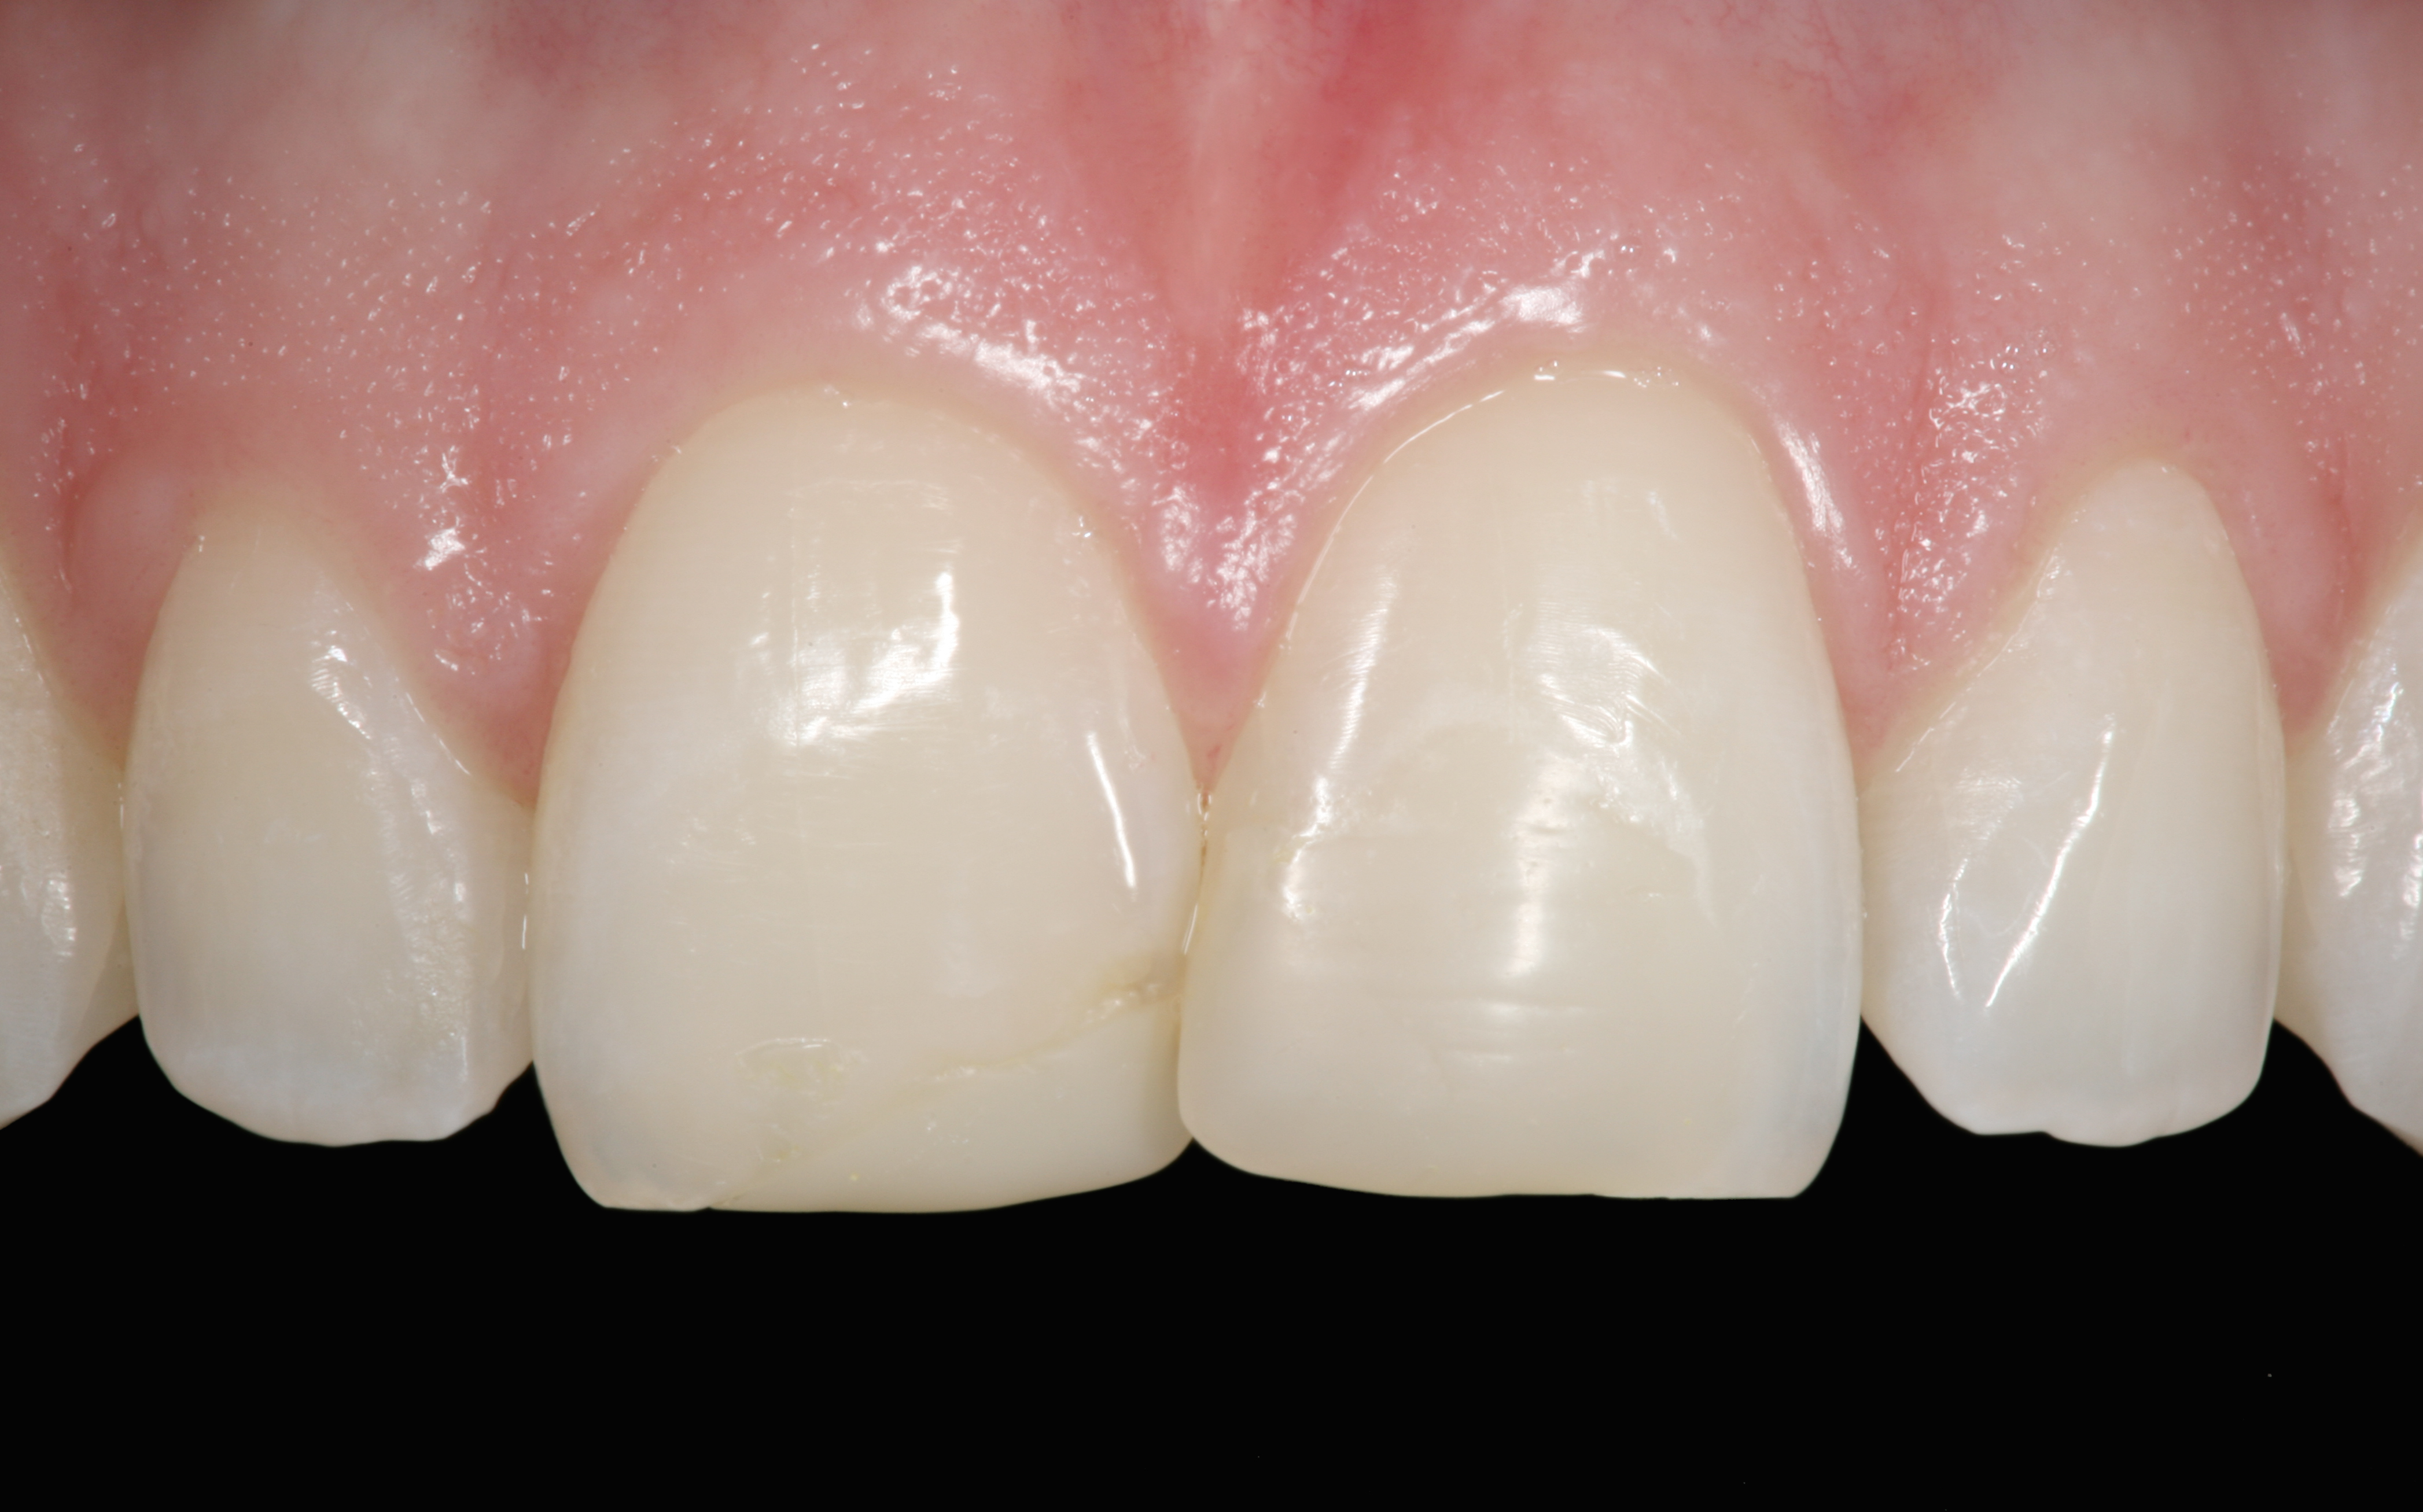

The clinical application of this protocol is illustrated in a patient situation where laminate veneers were placed on four maxillary incisors to replace lost tooth structure and restore function and esthetics. The failing restorations were removed, followed by a conservative veneer preparation (Figure 1 and Figure 2). The bonding surfaces of the feldspathic porcelain veneers were acid-etched with hydrofluoric acid for 2 minutes (Figure 3) and thoroughly rinsed. Then a silane coupling agent was applied (Figure 4). Figure 5 demonstrates the situation after bonding the veneers to the teeth with a composite resin luting agent.

The pretreatment situation.

Figure 1

Figure 13